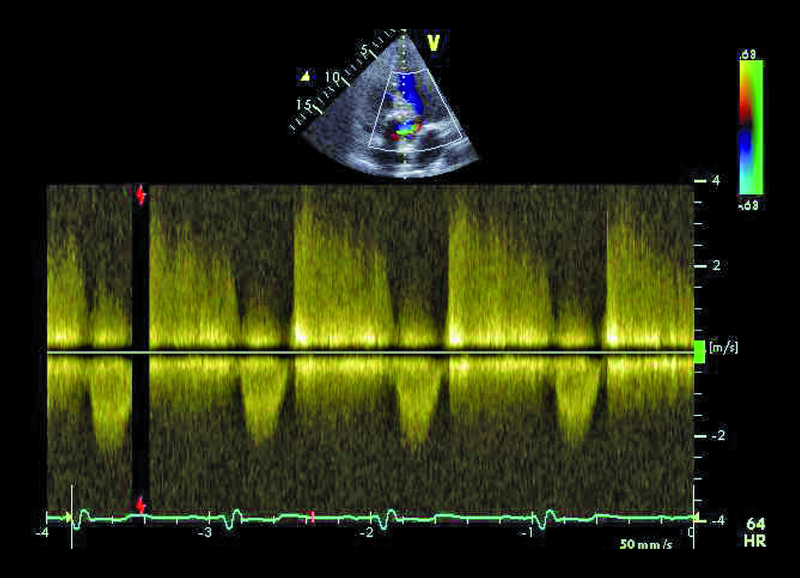

Mężczyzna, lat 25. Jakie patologie można rozpoznać na rycinach?

4. Mała niedomykalność aortalna (ryc. 3, 4).

5. Zwężenie drogi odpływu lewej komory (LVOTO) (ryc. 4, 5).